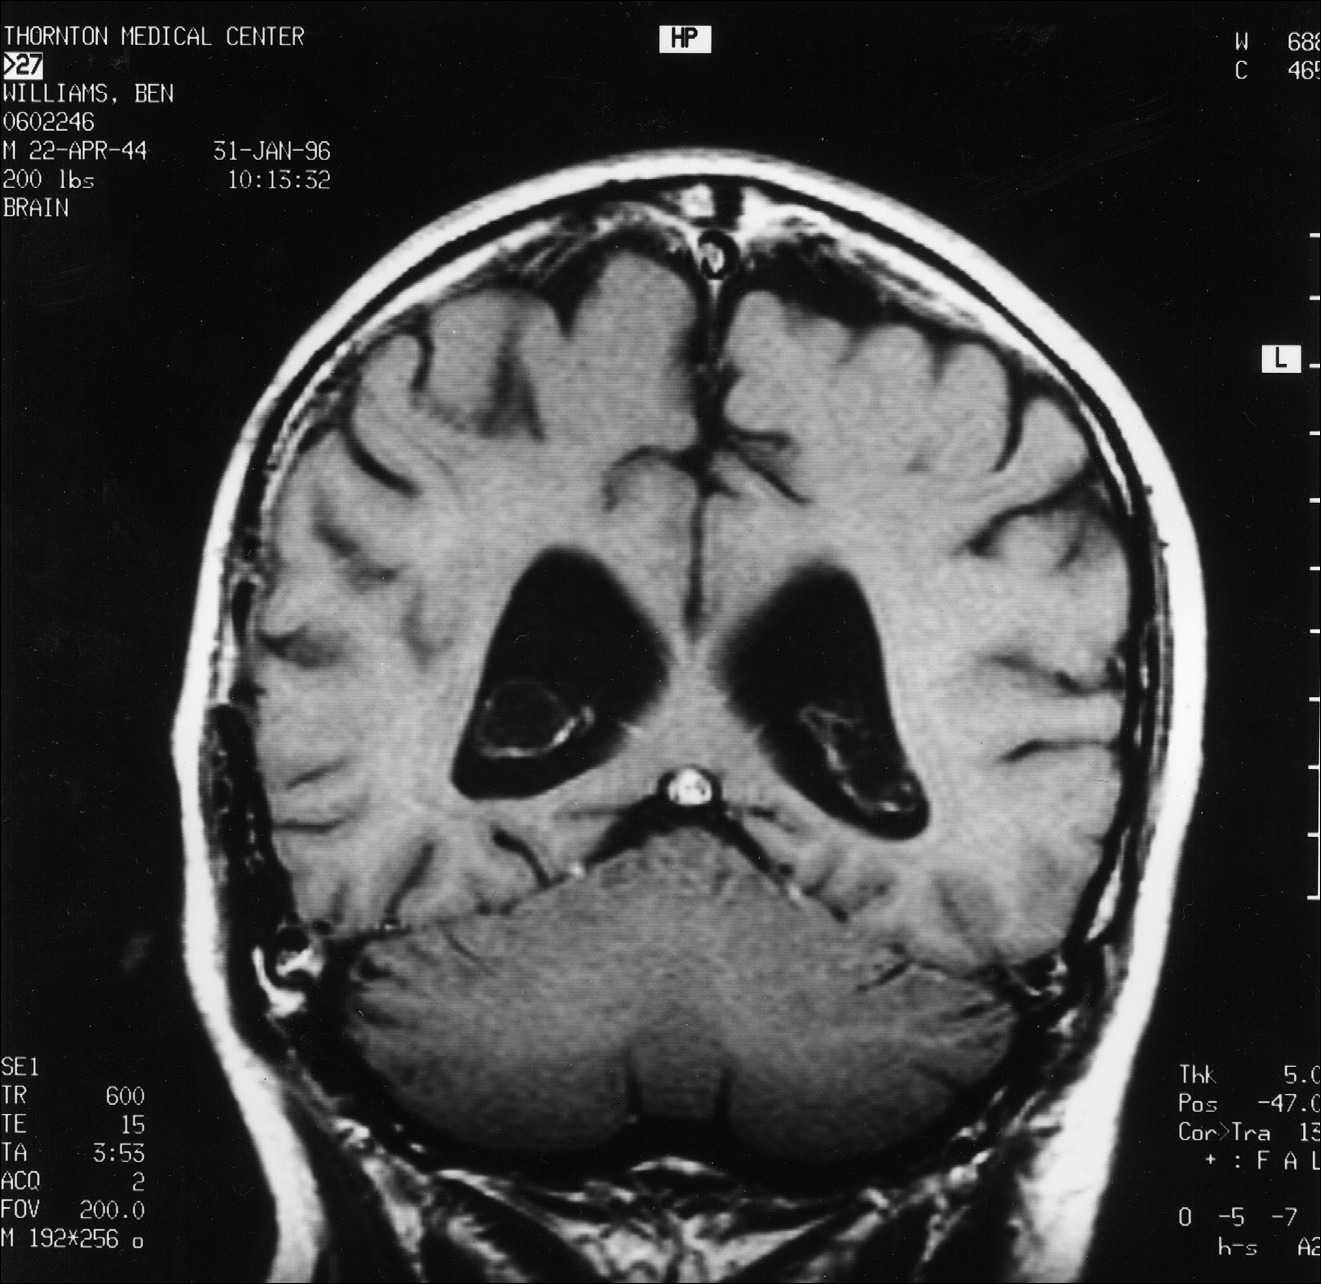

5 pav.

MRT pjūvis, atitinkantis pjūvius, parodytus 1 pav. ir 3 pav.

6 pav.

MRT pjūvis, atitinkantis pjūvius, parodytus 2 pav. ir 4 pav. Nors vis dar matomas nedidelis paryškinimas, jis atrodo esąs palei kietąjį dangalą, o ne žievėje.